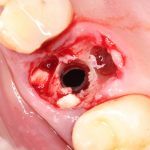

Кстати, обрати внимание на ширину альвеолярного гребня (левая картинка). Она чуть меньше 3 мм. Это объясняет, почему я засомневался в возможности установки имплантатов одновременно с остеопластикой. Понятно и без КЛКТ.

Наперво, мне нужно удалить разрушенный зуб и получить костный аутотрансплантат.

Возвращаемся к основной операционной области. Еще раз посмотрим на альвеолярный гребень, поофигеваем от его ширины и моих грандиозных планов: